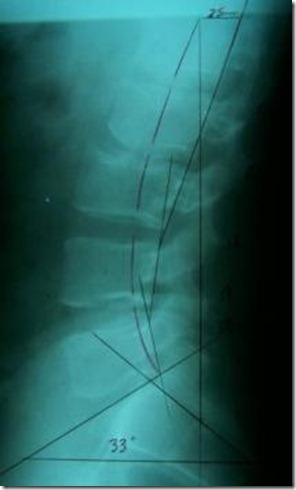

On his initial exam, the patient’s posture was inspected and revealed a posterior thoracic translated lateral posture. His A-P posture was relatively normal. A computerized range of motion test demonstrated restricted extension and restricted sacral/hip flexion resulting in an 8% impairment of normal movement. He also denoted an increase of his pain with left lumbar rotation and extension (Kemp’s Test). His radiographic exam was basically normal on the A-P view, but revealed a 25 millimeter posterior thoracic translation on the lateral view with a decreased sacral angle of 33 degrees (normal 40 degrees). He had a complete loss of lordosis at L1/L2 and L2/L3 (See X-ray #1).

Figures: X-ray #1 and #2